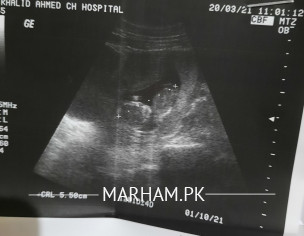

doctors please i need consultation. mn Rh negative hoon mry husband Rh positive. 1st pregnancy 12 w pregnant hoon ,mujy spotting ka problem hai .1st time pregnancy k 1st month mn hoi jbh mujy pta nhii ta mn pregnant hoon . aur abhi 12 th week mn . mn duphaston aur ivf injection lgva rhi. doctors please help kr dn ,mry mind mn hai mujy spotting k vja sy anti D injection abhi lgvana chyee ,k delivery k bad . ess ki abhi zarort hai k nhi? thanks ,I'm worried

Attach Photo here: